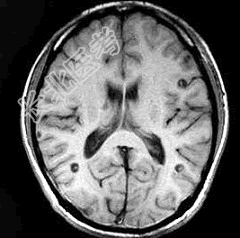

- 单项选择题患者,男, 29岁。头痛不适半个月。MRI扫描如图示。据此可作出下列最可能的诊断是 ( )

A、脑囊虫病

B、脑弓形虫病

C、脑结核

D、脑转移瘤